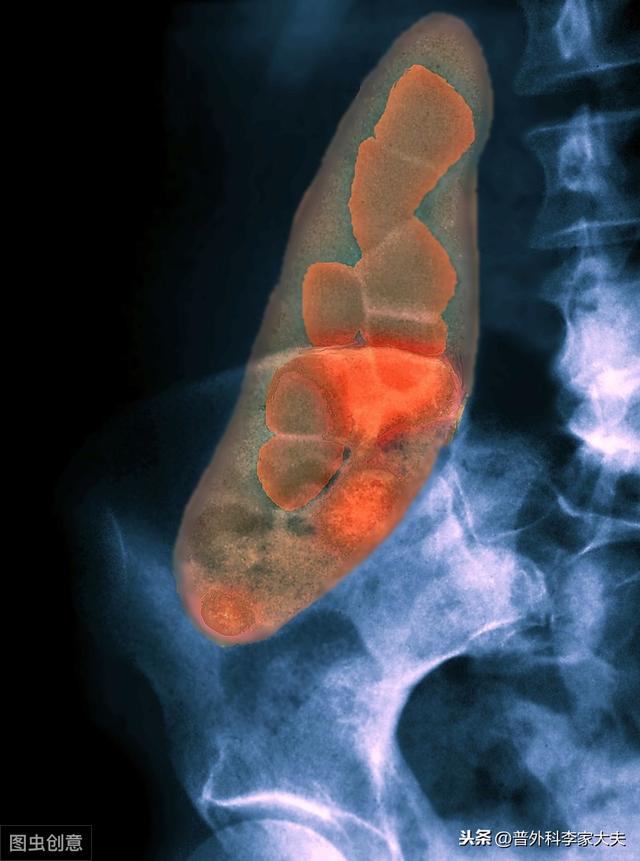

胆嚢炎の臨床的原因として最も多いのは胆嚢結石であり、生活水準の向上や人間ドックの普及に伴い、胆嚢結石の発生率は上昇傾向にある。健康診断で胆嚢結石が発見される人の割合は増加傾向にあり、無症候性胆嚢結石人口となる。臨床的には、胆嚢結石が発見される胆嚢炎患者が多くなっている。

胆嚢は右上腹部、肝臓の付け根にあり、体の胆道系の重要な部分である。胆嚢炎の典型的な症状は右上腹部の痛みで、その多くは疝痛である。患者さんの多くは脂っこいものを食べたことがきっかけで、右上腹部圧迫痛があり、マーフィー徴候が陽性です。腹部超音波検査では、明らかに肥大した胆嚢を見ることができ、同時に胆嚢結石を見つけることができます。

胆嚢結石は急性胆嚢炎の原因として最も可能性の高いものの一つであり、通常、胆石が突然閉塞したり、結石が胆嚢管に埋没した際に生じる激痛が原因である。 また、寄生虫やその代謝物が過去に流行した際に閉塞症状を呈することもあり、さらに胆嚢管の捻転、腫瘍、細菌感染も胆嚢炎の原因として一般的なものの一つである。

胆嚢結石は胆嚢炎の主要な病態因子であるため、コレステロール結晶の組成分析から胆嚢結石の組成がより多いと考えられる。